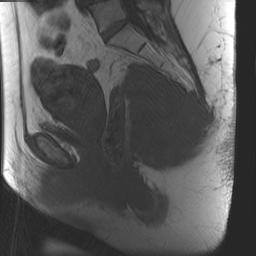

CT Scan / MRI

Useful to delineate tumour